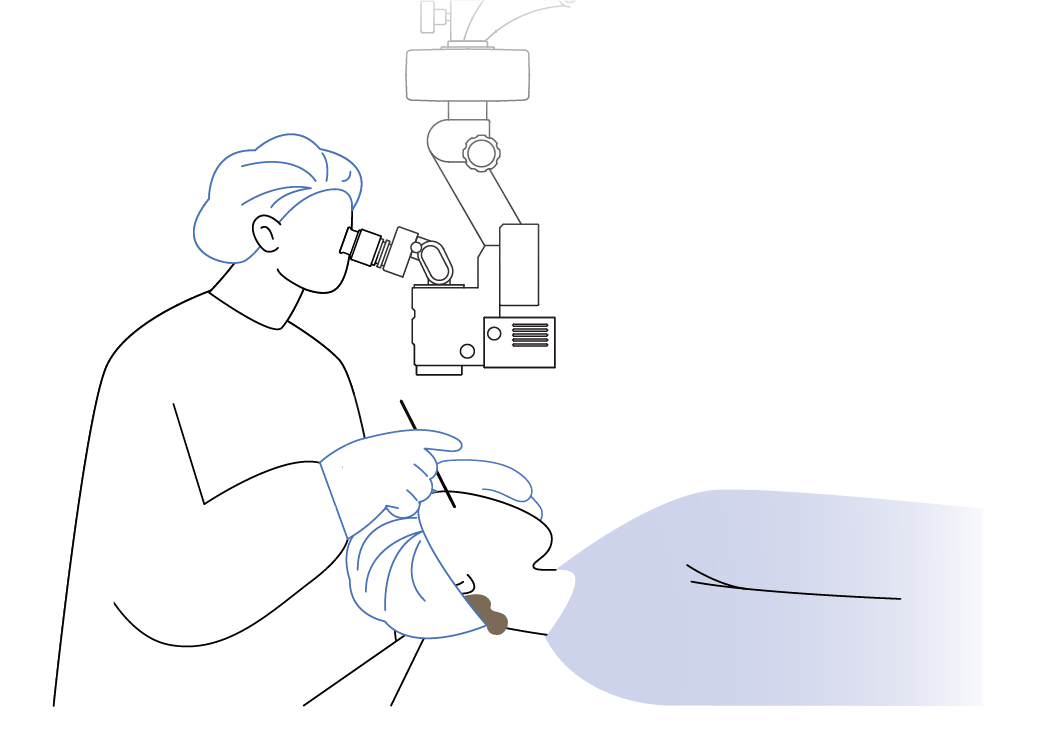

Operating Microscopes

OM-9

Supports a wide range of operations, from cataract surgery and retinal vitrectomy to out-patient procedures.

The optimized optical design and high-quality optical system maximize visibility during surgery and allow tiny tissues and structures to be identified clearly.

The illumination system uses high-luminance LED light to focus on contrast and color reproduction. The red reflex illumination mechanism provides ample reflected light from the fundus, resulting in high-quality red reflex and 3D observation images, which are essential for cataract surgery.

This design ensures a naturally bright and three-dimensional surgical field, making it easier to grasp the condition of the affected area.